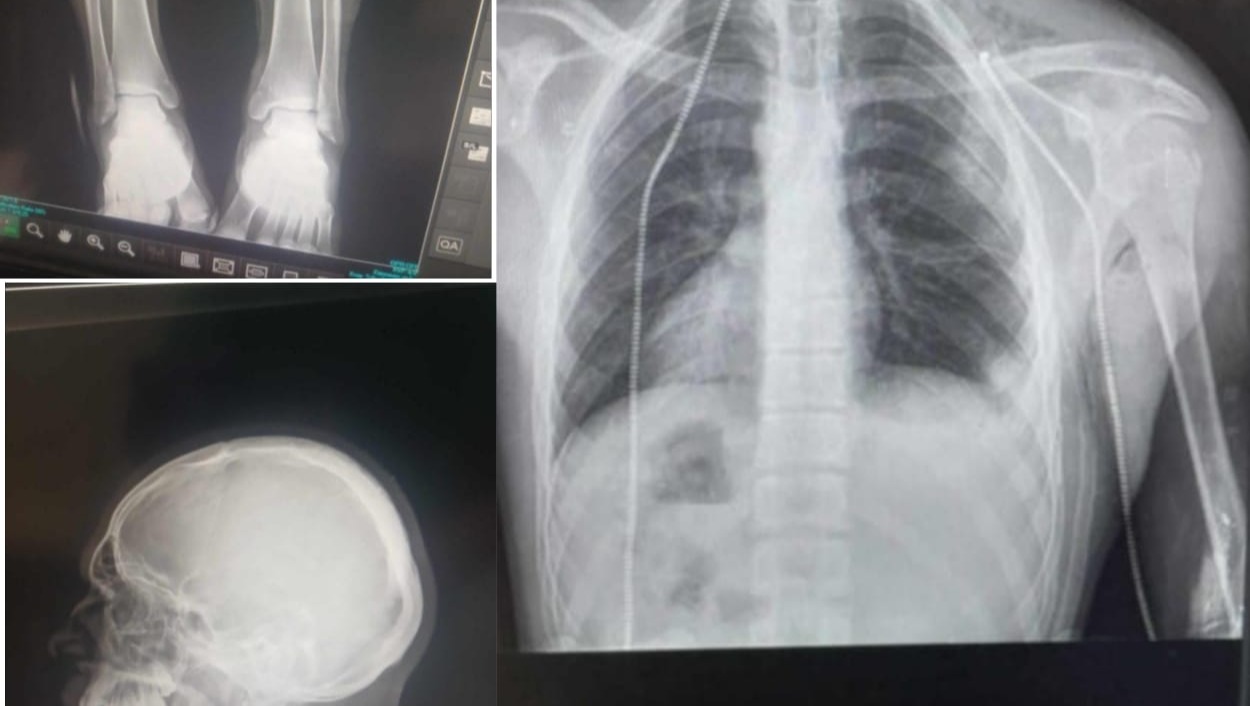

In the middle of the war, I was going to look for food to feed my sisters. We were bombed and I was seriously injured. I did not receive the necessary treatment. I now need your help so that I can feed my family, rebuild our destroyed house, and receive treatment outside Gaza.